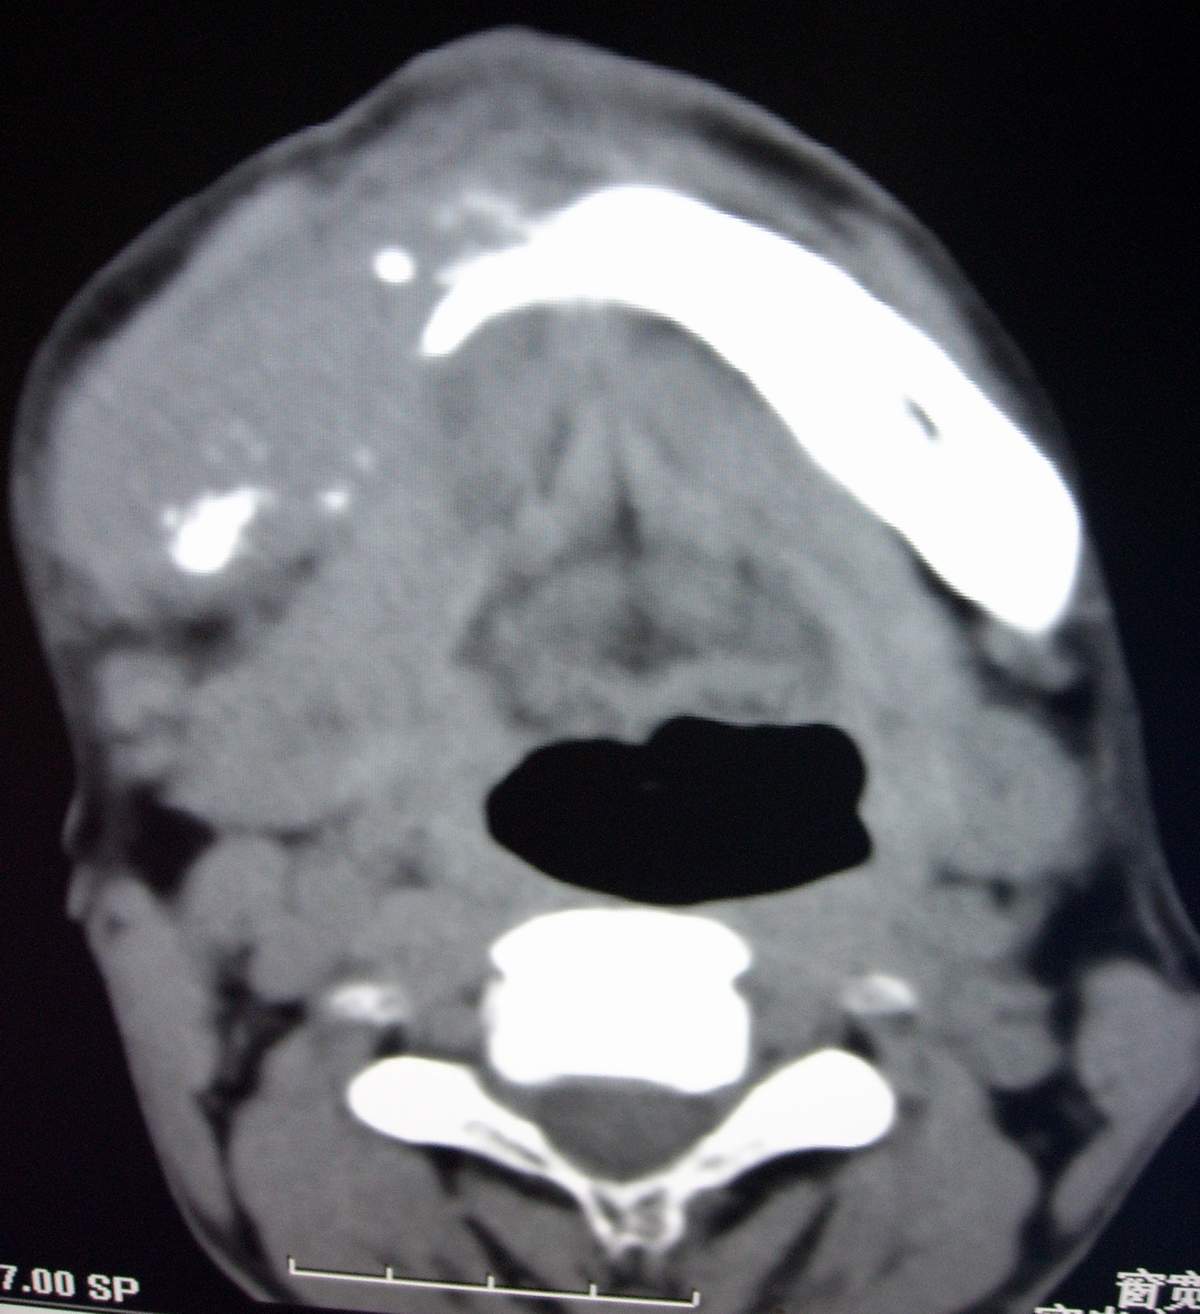

男,54岁,右下颌肿痛1月余。

考虑右下颌骨转移瘤或原发恶性肿瘤,右颈部淋巴结转移.

右侧下颌骨水平部及升支呈溶骨性破坏,无明显膨胀,周围见软组织肿块。

右下颌骨恶性骨肿瘤伴右颈部淋巴结转移。

右下颌骨溶骨性破坏,代之以团块状软组织影,内有斑片状瘤骨,边缘骨质有少量骨膜反应,考虑:右下颌骨骨肉瘤。期待病理。